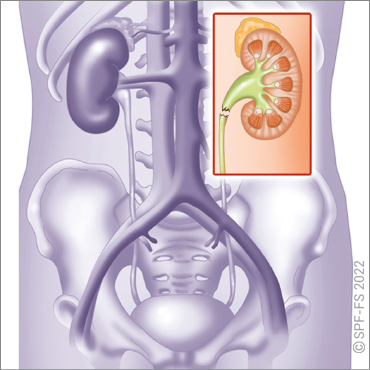

Généralités

Les reins